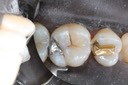

Wes Sato #14 pre-op

Wes Sato #14 amalgam removal